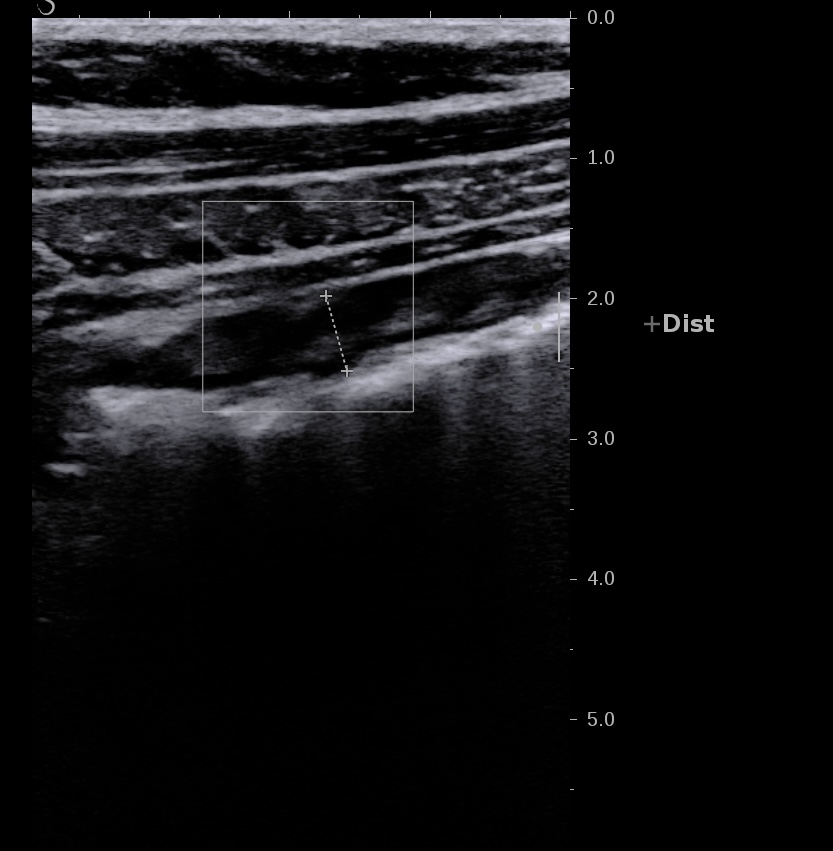

Forme plus chronique, épaississement très important de la sous muqueuse hyperéchogène par rapport à la muqueuse elle fait plus > 3/4 de la paroi

Forme chronique, aspect tubulisé du côlon, qui devient linéaire et rigide

Le doppler est souvent limité à la paroi (Limberg 1 et 2), la graisse peu ou pas infiltrée